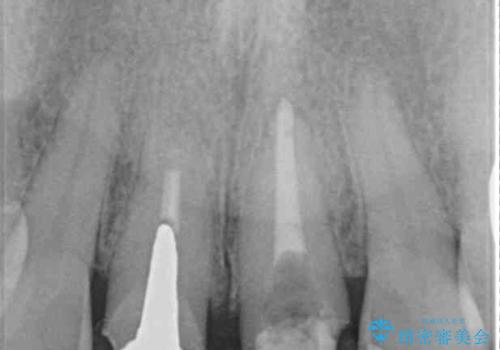

根管治療後に痛みは軽減しましたが、僅かな痛みが続くとのことで、レントゲン写真では病変は認められなかったものの、歯根端切除を行うこととしました。処置後は痛みは全くなくなり、安心して補綴治療を行うことができました。